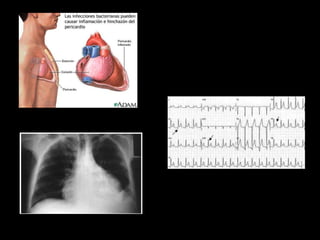

PERICARDITIS

LOS 5 GRANDES Síndromes coronarios agudos.  Disección aórtica.  Embolismo pulmonar.  Neumotórax a tensión.  Ruptura esofágica.